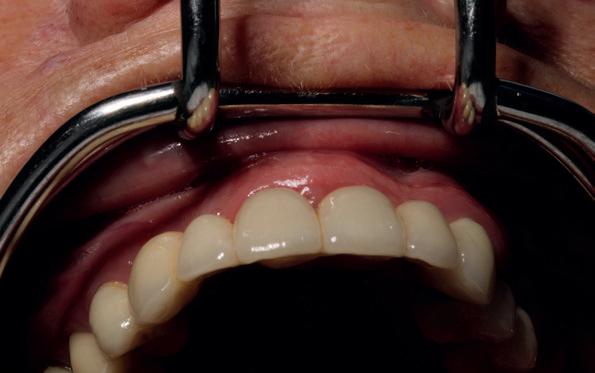

Deze casus beschrijft een uitgebreide immediate implantaatbehandeling bij een patiënt die door meerdere collega’s werd geweigerd. Niet omdat de mogelijkheden ontbraken, maar omdat de complexiteit vroeg om een perfect afgestemde samenwerking. Het verhaal laat zien hoe de assistent in zo’n traject veel meer is dan een uitvoerende kracht of “mal”, maar een dynamische surgical guide die het proces mede stuurt, bewaakt en mogelijk maakt.De patiënt: wanneer alles samenkomt

Ze kwam binnen op een dinsdagochtend, iets voor achten. Een vrouw van begin zeventig, met een zachte stem en ogen die meer vertelden dan haar woorden. Ze vertelde dat ze een eigen B&B had en dat ze zich nauwelijks kon voorstellen gasten te ontvangen zonder tanden. Op dit moment kon ze echter nauwelijks lachen. “Het doet pijn… en het ruikt soms ook niet goed,” zei ze bijna verontschuldigend. Haar oude bovenbrug, die ze al meer dan twintig jaar droeg, was langzaam maar zeker ingestort. Er was sprake van cariës onder meerdere pijlers, pusafvloed,

chronische ontsteking en een brug die mobiel was en elke beet pijnlijk maakte. Ze had inmiddels meerdere tandartsen bezocht. Drie hadden haar geweigerd. Te complex. Te veel wensen. Te onvoorspelbaar.

De kern van haar vraag was eenvoudig en tegelijkertijd uitdagend: Is het mogelijk om mijn huidige brug te dupliceren en een nieuwe brug te vervaardigen met minder complicaties?